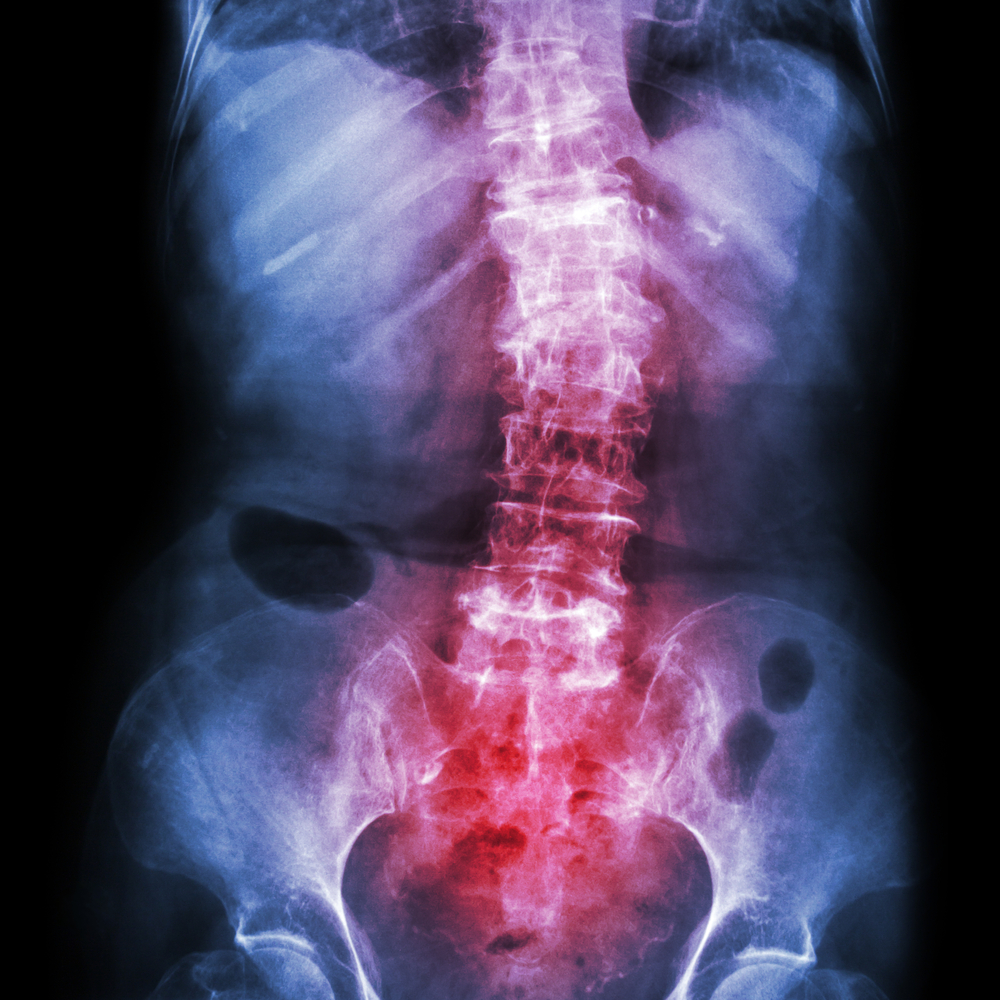

Norint geriau suvaldyti ankilozinį spondilitą, svarbu kuo daugiau apie šią ligą išmokti. Suprasdami savo būklę bei įvairius jos simptomus, galite sustiprinti savo savikontrolę ir pagerinti kasdienio gyvenimo kokybę.

Nors pats terminas gali atrodyti painus, ankilozinis spondilitas – kompleksinė ir daugeliui individualiai pasireiškianti būklė. Kiekvienam ji gali sukelti skirtingus simptomus. Kruopščiai renkantis informaciją, bendraujant su medikais ar konsultuojantis su specialistais, galima pasirūpinti savimi daug efektyviau. Informacijos gausa leidžia lengviau susidoroti su kasdieniais sunkumais, būti aktyviu savo gydymo procese ir gerinti savijautą.